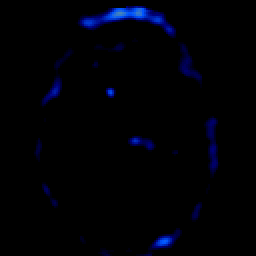

glioma overlay -- Slice #14

[Home][Help][Clinical] Slice 14

Click on sagittal image to select slice. Click on thin tickmark to change timepoint, or thick tickmark for overlay.